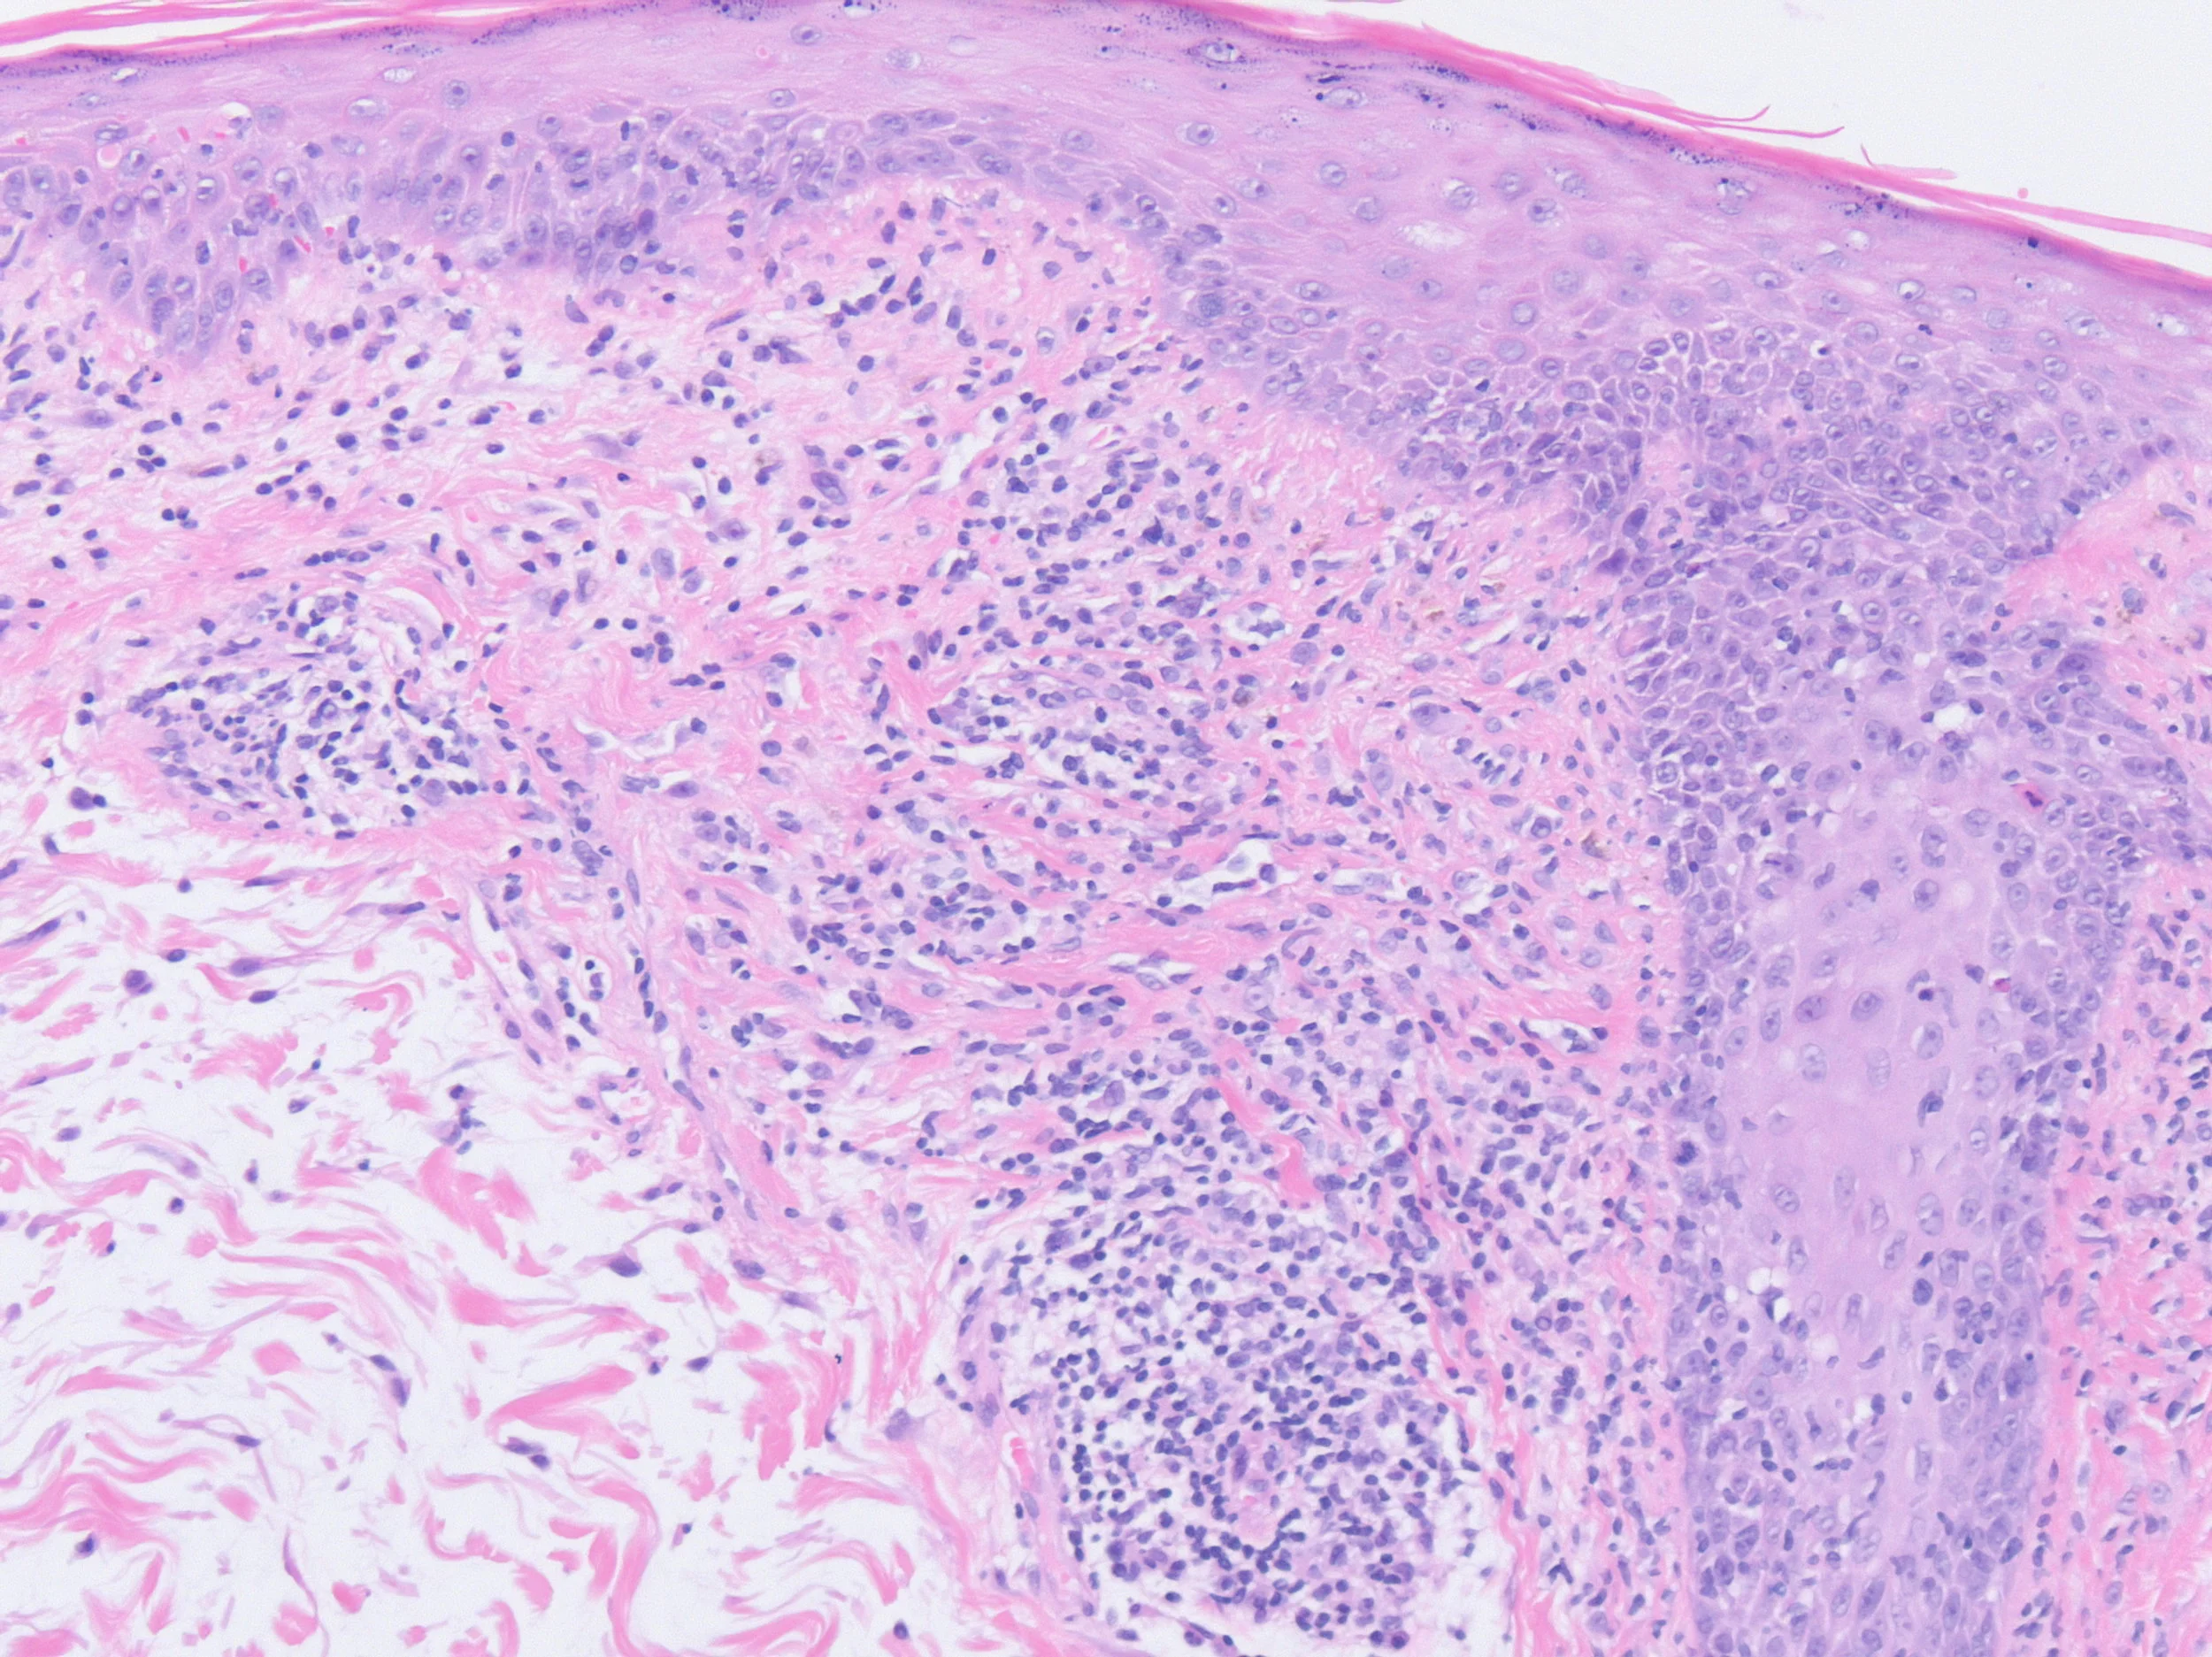

- 45 yo female, referral from Rheumatology re ‘is this psoriasis?’

- 3 month history of asymptomatic, red tumid plaques over posterior neck and cape regions (photosensitive distribution) and throughout scalp (with hair loss).

- 6 week history of painful inflammatory arthritis (small joints hands) and systemic symptoms (fatigue, morning stiffness).

Left Shoulder Tip

Right Scalp